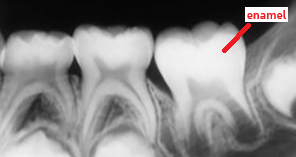

enamel

radiopaque